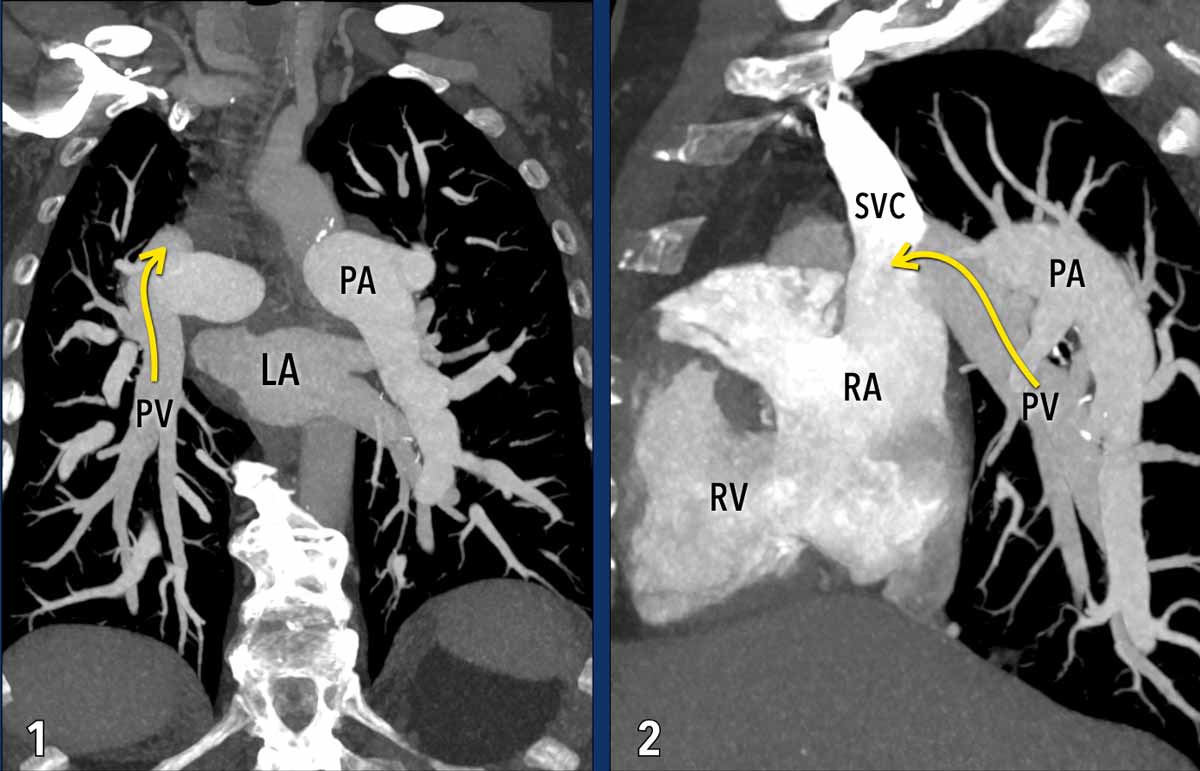

Partial anomalous pulmonary venous return (PAPVR)

In partial anomalous pulmonary venous return, one or more pulmonary veins abnormally drain into the systemic venous  circulation (mainly into the superior vena cava on the right, and into the left brachiocephalic vein on the left side), instead of the normal drainage into the left atrium.

Depending on the shunt volume, chronically increased pulmonary circulation from this shunt can result in endothelial injury, smooth muscle hypertrophy, and vascular fibrosis, ultimately leading to elevated pulmonary vascular resistance, and the development of pulmonary hypertension.

Illustration

In this case, most pulmonary veins drain normally into the left atrium (green arrows).

However, the right upper lobe pulmonary vein is anomalous and drains via the superior vena cava into the right atrium rather than the left atrium (red arrow).

This anomalous venous return creates a left-to-right shunt, leading to volume overload of the right atrium and right ventricle.

These images are of a patient with pulmonary hypertension secondary to partial anomalous pulmonary venous return (PAPVR).

Imaging Findings

The right lower lobe pulmonary veins are not connected to the left atrium (LA) but instead drain into the superior vena cava (arrows).

Note the bilateral dilatation of the pulmonary arteries, consistent with elevated pulmonary arterial pressure.